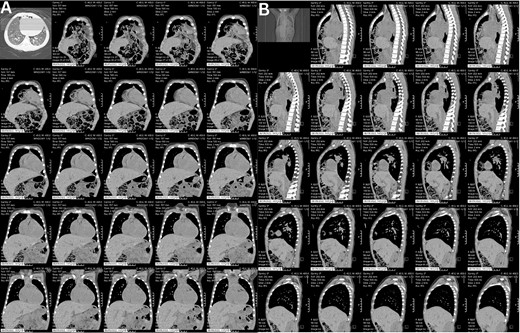

A preoperative assessment revealed an unexpected diaphragmatic hernia found incidentally on a routine chest X-ray (Fig. 1). This led to further tests, including a chest computed tomography (CT), which showed a central diaphragmatic defect with part of the transverse colon herniated into the chest (Fig. 2). Additionally, echocardiography found a perimembranous VSD with bidirectional shunting and mild tricuspid valve regurgitation. Cardiac catheterization confirmed reactive pulmonary vascular resistance.

These CT chest scans in the coronal (A) and sagittal (B) planes, showing an anterior central diaphragmatic defect measuring 4.3 cm × 2.8 cm (TR × AP) with intrathoracic herniation of part of the transverse colon.